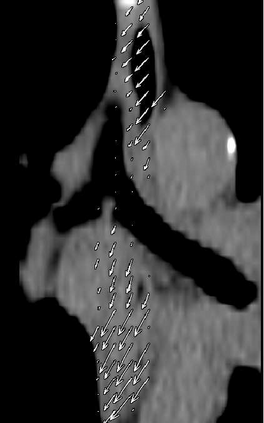

Stereotactic body radiation therapy allows for a precise and accurate dose delivery. Organ motion during treatment bears the risk of undetected high dose healthy tissue exposure. An organ very susceptible to high dose is the oesophagus. Its low contrast on CT and the oblong shape renders motion estimation difficult. We tackle this issue by modern algorithms to measure the oesophageal motion voxel-wise and to estimate motion related dosimetric impact. Oesophageal motion was measured using deformable image registration and 4DCT of 11 internal and 5 public datasets. Current clinical practice of contouring the organ on 3DCT was compared to timely resolved 4DCT contours. The dosimetric impact of the motion was estimated by analysing the trajectory of each voxel in the 4D dose distribution. Finally an organ motion model was built, allowing for easier patient-wise comparisons. Motion analysis showed mean absolute maximal motion amplitudes of 4.24 +/- 2.71 mm left-right, 4.81 +/- 2.58 mm anterior-posterior and 10.21 +/- 5.13 mm superior-inferior. Motion between the cohorts differed significantly. In around 50 % of the cases the dosimetric passing criteria was violated. Contours created on 3DCT did not cover 14 % of the organ for 50 % of the respiratory cycle and the 3D contour is around 38 % smaller than the union of all 4D contours. The motion model revealed that the maximal motion is not limited to the lower part of the organ. Our results showed motion amplitudes higher than most reported values in the literature and that motion is very heterogeneous across patients. Therefore, individual motion information should be considered in contouring and planning.